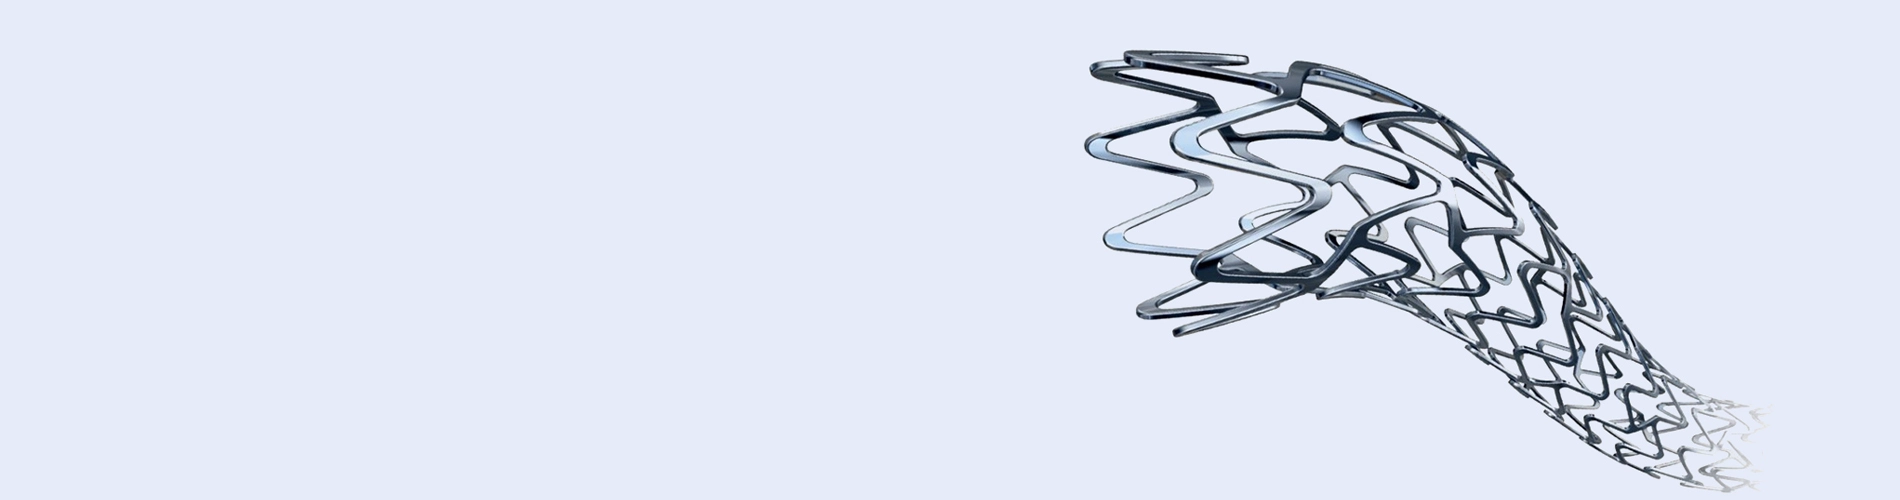

A stent is an expandable metal mesh tube to treat narrowed or blocked blood vessels, including coronary arteries. It is designed to hold open the artery walls and improve blood flow to the heart. The stent gets placed in the blocked artery during a stent procedure or coronary angioplasty, an interventional procedure used to treat coronary artery disease.

The stent procedure in the heart, known as percutaneous coronary intervention (PCI), is a minimally invasive procedure to treat narrowed or blocked coronary arteries effectively. During the procedure, a thin catheter gets inserted into an artery through the groin or wrist and guided to the blocked artery in the heart. A small balloon at the catheter’s tip gets inflated to help widen the artery and improve blood flow.